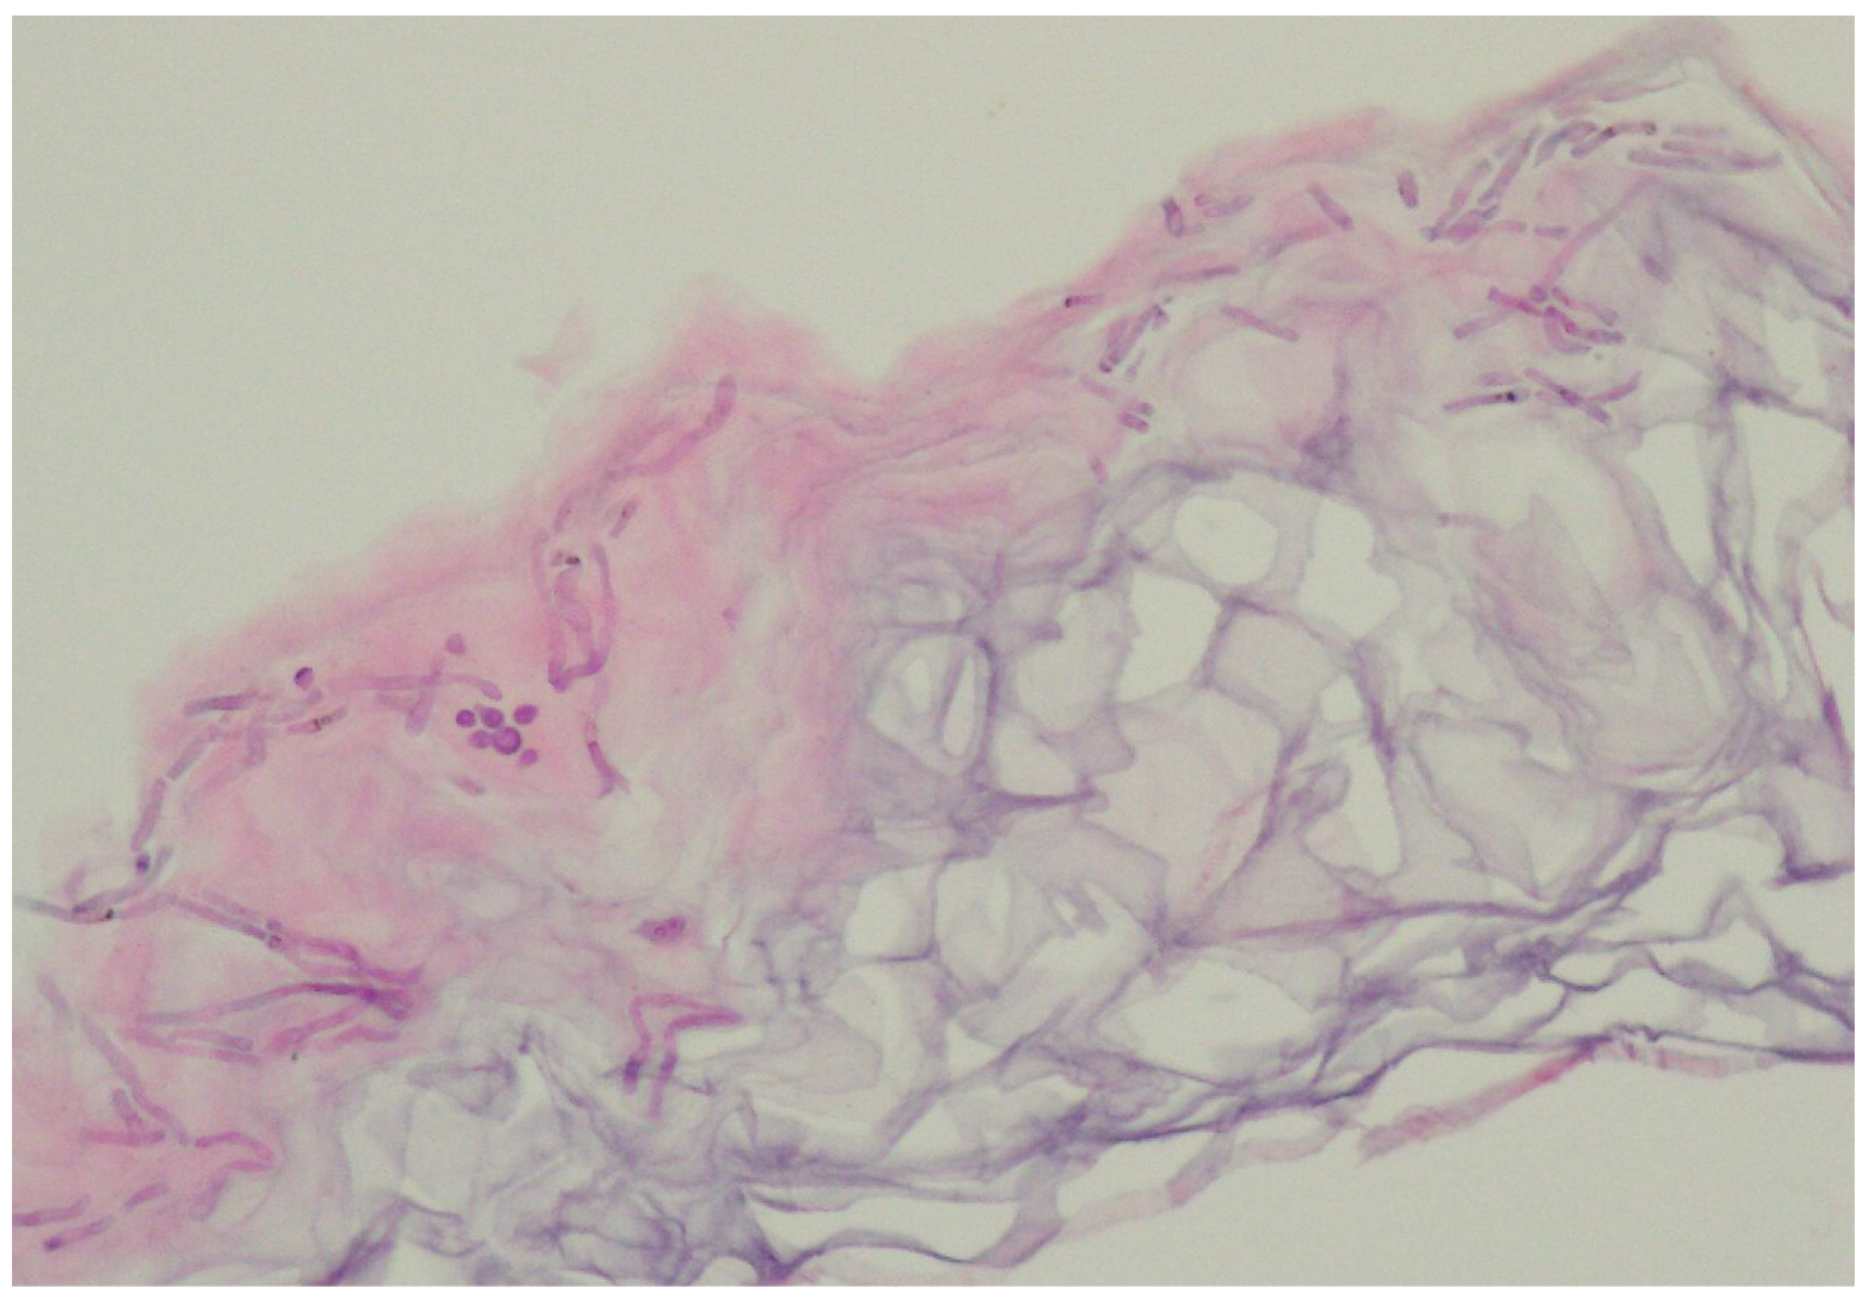

6.3. Histopathology

- Guarner, J.; Brandt, M.E. Histopathologic diagnosis of fungal infections in the 21st century. Clin. Microbiol. Rev. 2011, 24, 247–280. [Google Scholar] [CrossRef] [PubMed]

- Allen, H.B.; Charles, C.R.; Johnson, B.L. Hyperpigmented tinea versicolor. Arch. Dermatol. 1976, 112, 1110–1112. [Google Scholar] [CrossRef]